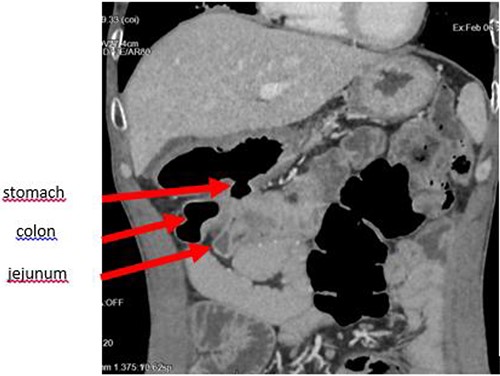

The enteroscan showed a large fistula between the anterior face of the stomach, the jejunum and the transverse colon (Figs 2 and 3). The diagnosis of GJF was then established. The patient underwent surgery. A revision gastrectomy, truncal vagotomy and segmental resection of the jejunum and transverse colon with Roux-en-Y reconstruction were performed. During the follow-up, the patient remained well and gained weight.

Axial section showing the large GJF with stranding of the surrounding fat.